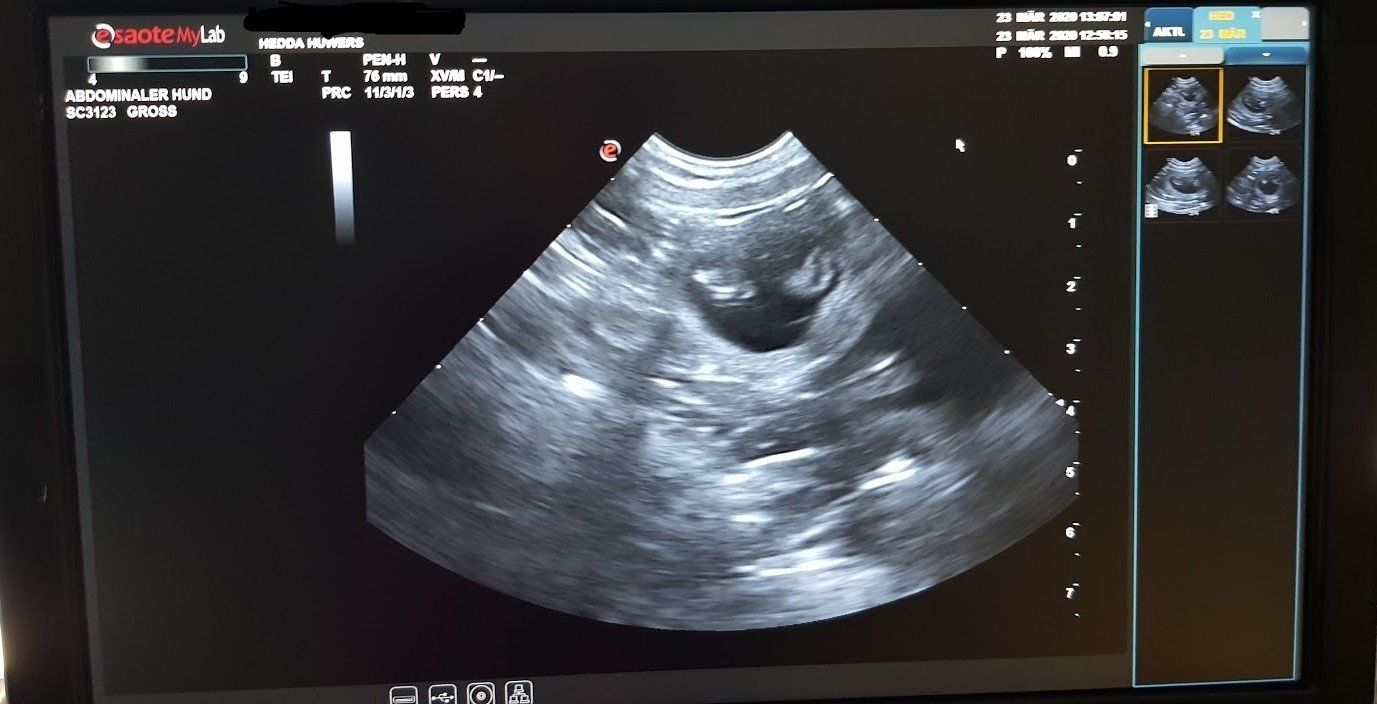

23.März 2020

Tag 32

Wir waren heute beim Ultraschall.

Endlich Gewissheit.

Juhu!!!!

Unsere Hedda bekommt Babys ♥♥♥

Der Tierarzt war sehr zufrieden mit ihr, leider konnten wir die genaue Anzahl der Welpen nicht sehen. Hedda wiegt jetzt 28kg also kein Leichtgewicht.

Um den 24.April werden die kleinen Mäuse das Licht der Welt erblicken. Wir sind schon voller Vorfreude ☺☺☺